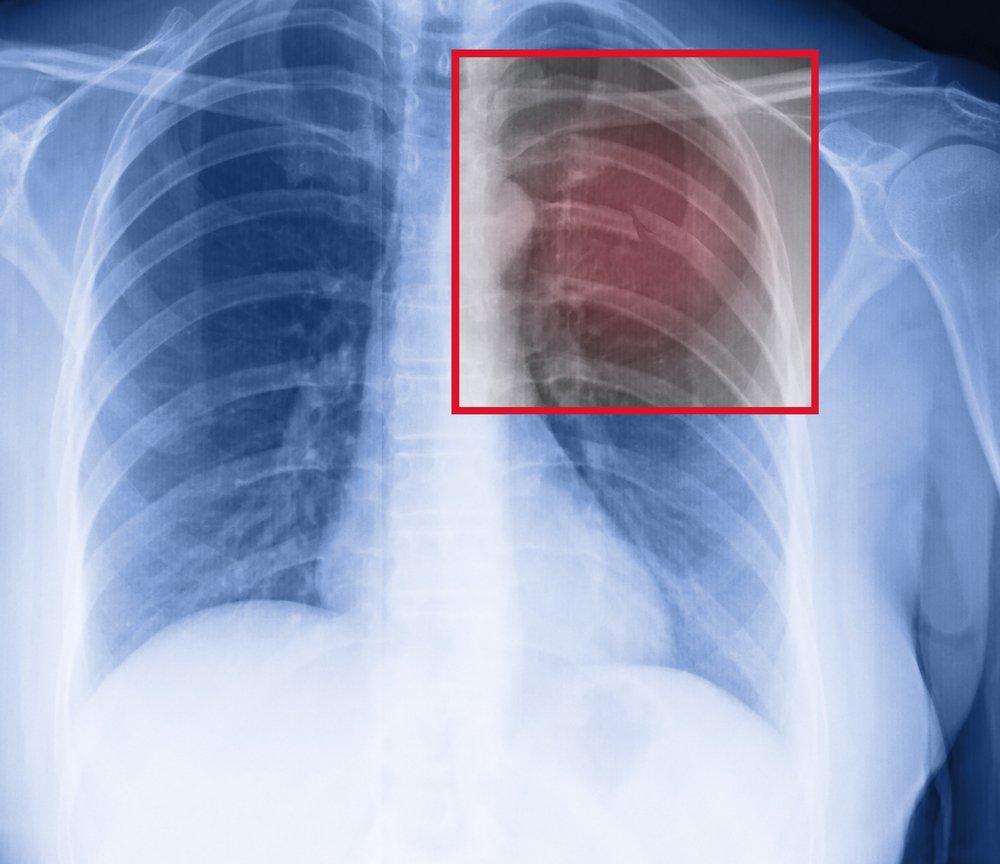

Broken Human Ribs

Xray Of Broken Ribs Broken Ribs Va Disability This list includes both analogous and equivalent va. This list of va disability conditions, comprised of 923 eligible conditions, is arranged alphabetically from a to z. Both are eligible for va disability benefits depending. Under diagnostic code 5321, a 0 percent evaluation is assigned for a slight muscle disability of group xxi (muscles of respiration);. Va will consider the information. Broken Ribs Va Disability.